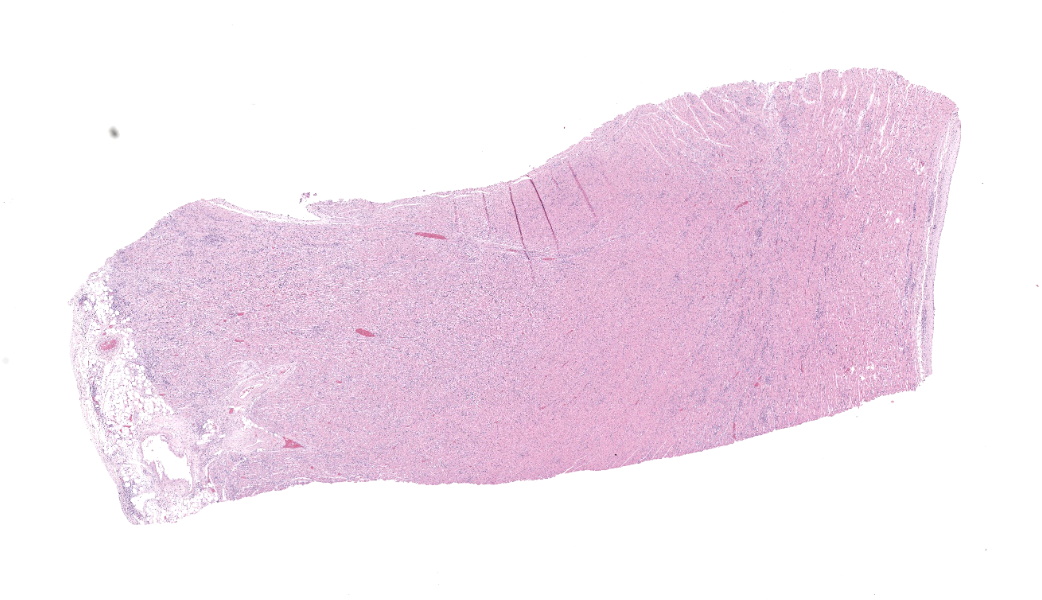

Expanding and infiltrating all layers of the heart, with the greatest severity in the myocardium, are large numbers of plasma cells, lymphocytes, and macrophages. Cardiomyocytes in areas of inflammation are multifocally hypereosinophilic, shrunken, and have striation loss with fragmented to absent nuclei (necrosis). There is mild, multifocal, interstitial fibrosis often associated with cardiomyocyte degeneration and inflammation. Throughout the myocardium, there are occasional cardiomyocytes that contain intrasarcoplasmic, variably sized (up to 100 μm in length) pseudocysts with numerous, 2-3 μm, round protozoal amastigotes.Contributor's Morphologic Diagnoses:

Heart: Severe, multifocal, chronic-active, lymphoplasmacytic and histiocytic pancarditis with intrasarcoplasmic pseudocysts containing amastigotesContributor's Comment: